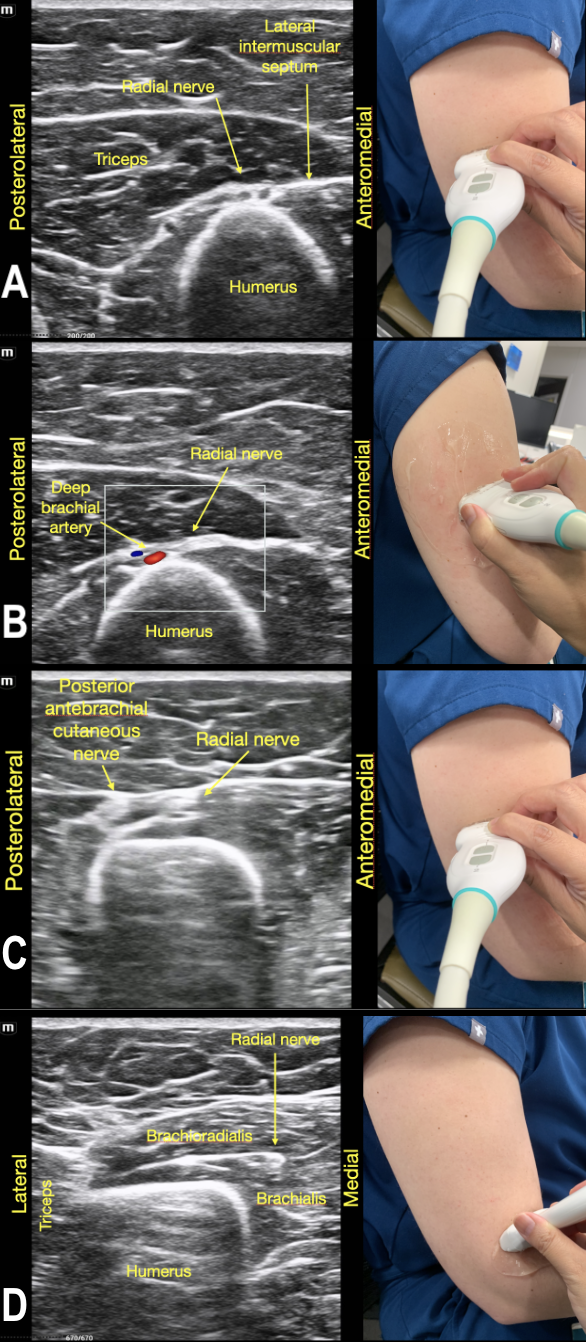

To identify the radial nerve in the mid-humerus position, have the patient in a seated position with the arm extended or held over the abdomen with the elbow flexed. Start with the probe placed transverse across the posterolateral mid-humerus and identify the radial nerve as a hyperechoic honeycombed structure lying directly on top of the humerus. At this point the radial nerve lies within the spiral groove and is also seen adjacent to the deep brachial artery. (Figure 7A)

As the probe is moved distally along the spiral groove, the posterior cutaneous nerve of the forearm can be seen branching from the radial nerve just prior to the lateral intermuscular septum (Figure 7D). In Video Clip 1, the radial nerve passes from the triceps into the biceps through the linear echogenic lateral intermuscular septum, which is a hyperechoic connective tissue layer separating the dorsal and anterior compartment of the arm.13

RadialNerve-Image1 Aug2024.pngFigure 1. Radial nerve lying directly on top of the mid-humerus adjacent to the deep brachial artery.

RadialNerve-Image6 Aug2024.pngFigure 6. Radial nerve joins the posterior cutaneous branch of the forearm proximal to the lateral intermuscular septum in the dorsal compartment of the arm.